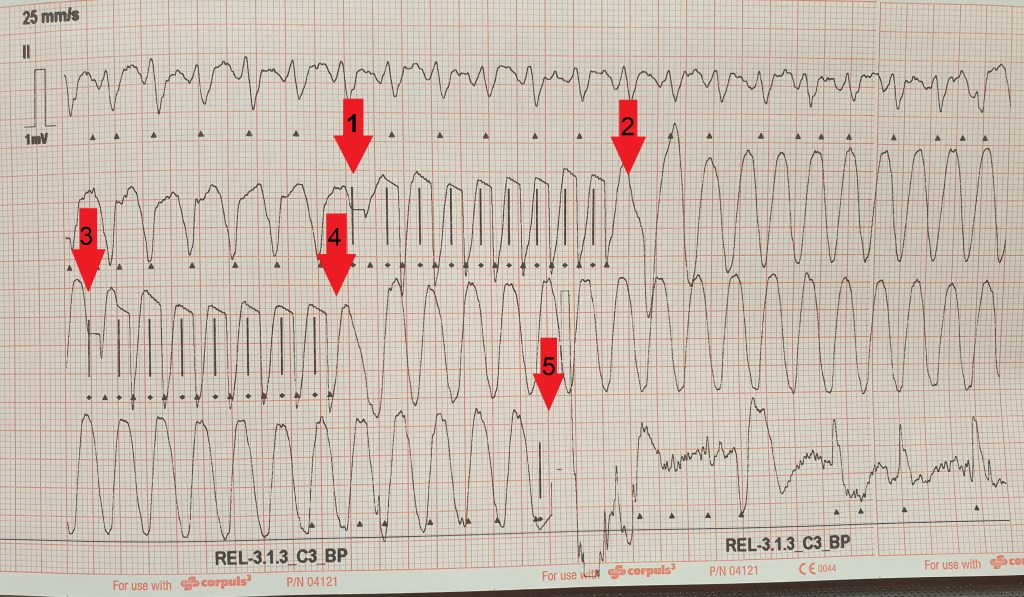

Man sieht zu Beginn eine regelmäßige Breitkomplextachykardie. Bei älteren Patienten insbesondere mit kardialen Grunderkrankungen ist eine ventrikuläre Tachykardie deutlich wahrscheinlicher als die Differentialdiagnose einer supraventrikuläre Tachykardie mit aberranter Überleitung (siehe unser Video zum Thema VT).

Beim 1. Pfeil (siehe Bild unten) sieht man eine zunehmende Frequenz, die durch die EKG-Software als Schrittmacheraktionen mit senkrechten Strichen gekennzeichnet werden. Die Patientin hat also ein implantiertes Device (einen Schrittmacher?), das stimuliert. Es stimuliert schneller als die vorherige Herzfrequenz im Rahmen eines so genannten „overdrive pacing“, im Anschluss ist die Herzfrequenz noch schneller und eine fast Sinus-förmige Kurve erscheint nun (2. Pfeil), hierbei handelt es sich um Kammerflattern!

Je nach kardialer Leistungsfähigkeit kann der Auswurf (= Puls) trotz der Frequenz noch ausreichen, dass die Patientin wach bleibt. Das Kammerflattern erkennt das implantierte Device und versucht ein zweites Mal ein „overdrive pacing“ (3. Pfeil), ebenfalls mit ausbleibendem Erfolg, denn es besteht im Anschluss weiterhin Kammerflattern (4. Pfeil).

Nach zwei erfolglosen Versuchen schockt der implantierte Defibrillator/ICD (es ist wohl doch nicht nur ein Schrittmacher…) nun (5. Pfeil) und kann im Anschluss daran einen normofrequenten Rhythmus (hier a.e. Vorhofflimmern) etablieren. Während des Schocks war die Patientin wach gewesen und hatte somit den kurzen, aber starken Thoraxschmerz bei vollem Bewusstsein mitbekommen.